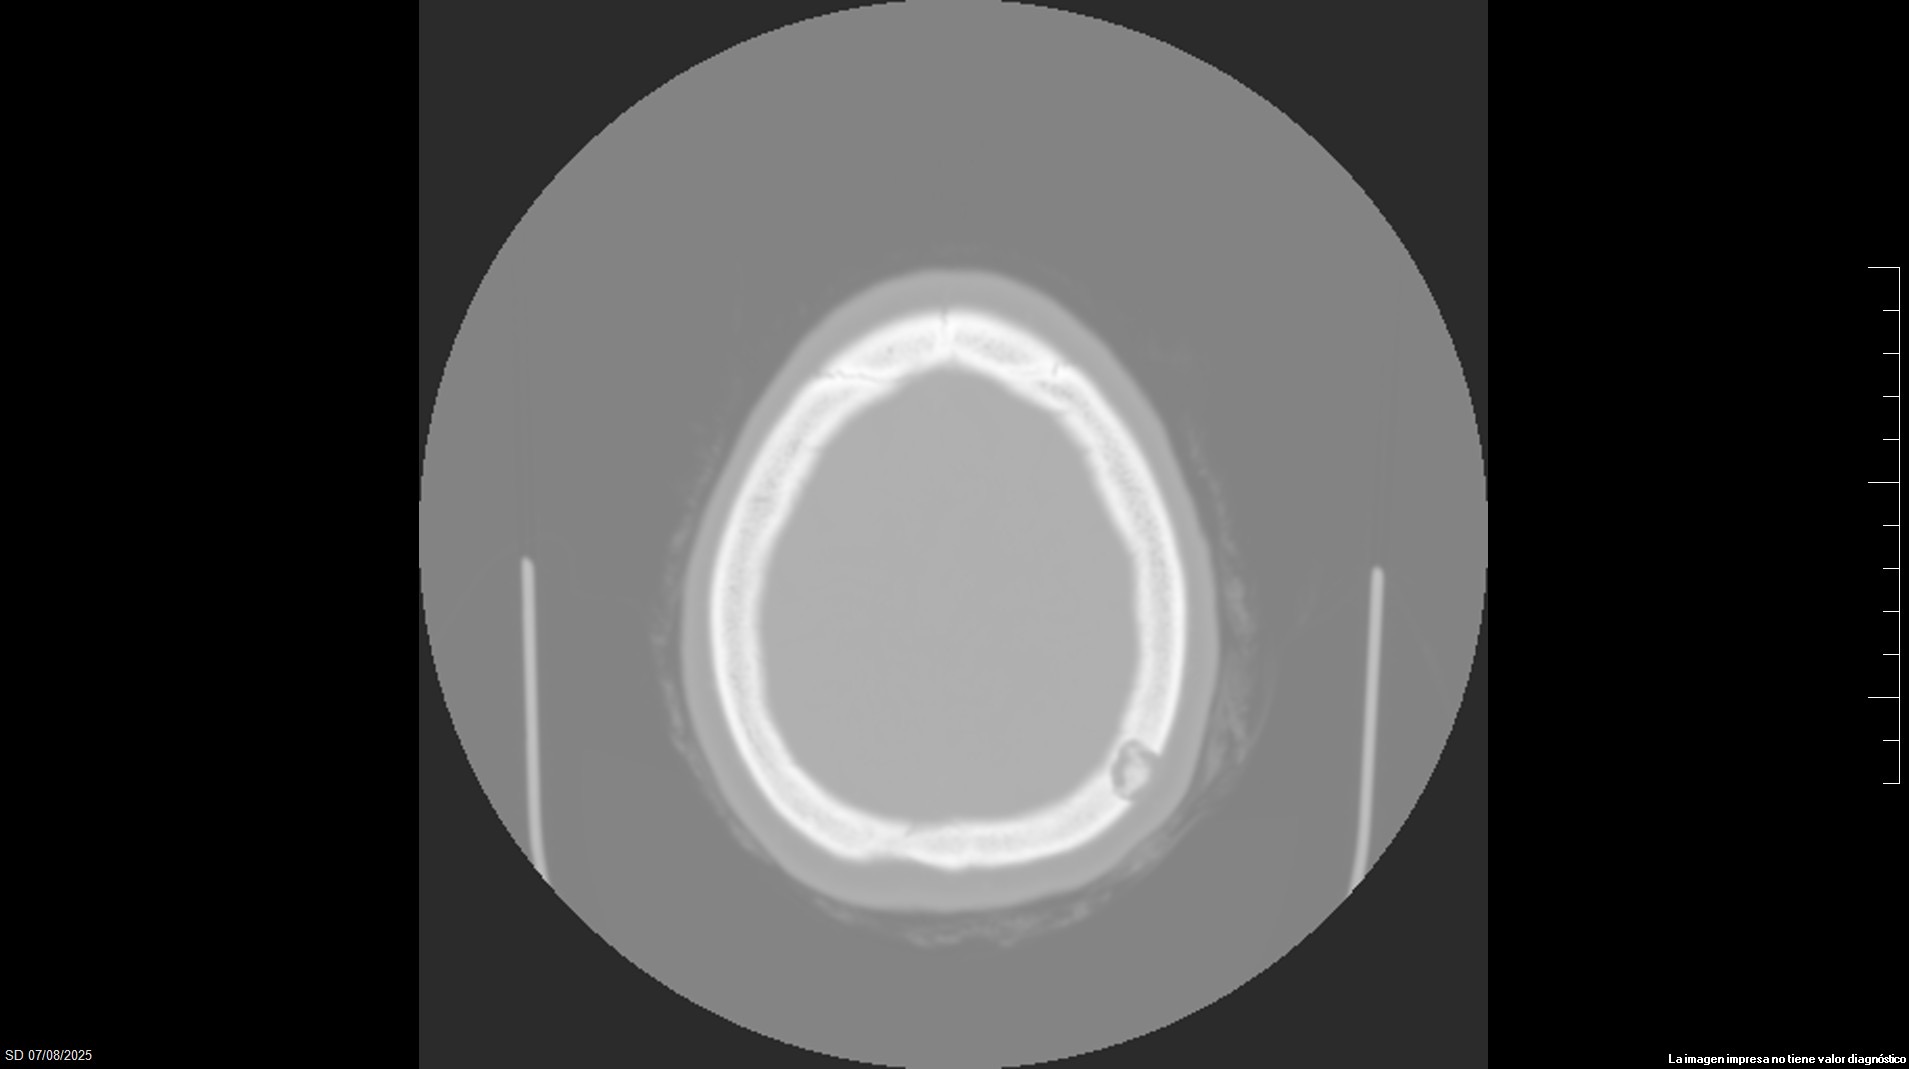

Pruebas complementarias

Ante hallazgos solicitamos TAC preferente: Lesión occipital izquierda de 1,2 cm, única, lítica, con secuestro óseo en su interior, sin componente de partes blandas intra o extracraneal. Compatible con granuloma eosinofílico.